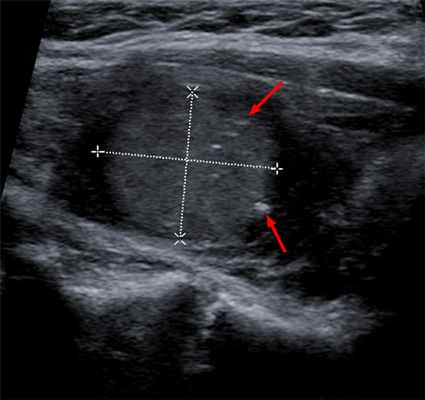

Ультразвуковое исследование щитовидной железы и регионарных лимфатических узлов - наиболее точный метод диагностики узловых образований.

Исследование щитовидной и паращитовидных желез, позволяющее оценить их структуру, а также обнаружить патологические изменения этих органов и регионарных лимфоуз.

Однако определить, является ли узел злокачественным, можно только по результатам тонкоигольной биопсии.

Тонкоигольную аспирационную биопсию узлов щитовидной железы (ТАБ) назначают, если обнаруженный узел больше 1 см. При меньших узлах ее выполняют при наличии подозрительных симптомов, которые позволяют заподозрить онкологическое заболевание.

ТАБ - безопасное исследование, занимающее несколько минут и не требующее специальной подготовки. Для забора биоматериала используют тонкую иглу, поэтому анестезия не требуются. Биопсию узлов щитовидной железы проводят только под контролем УЗИ.

Мы используем современную диагностику рака щитовидной железы. Заподозрить опухоль врач может при пальпации щитовидной железы и шейных лимфоузлов. При наличии уплотнений или жалоб пациента, врач назначает ультразвуковое исследование органа.

При подозрении на рак щитовидной железы под контролем УЗИ делаем тонкоигольную аспирационную пункционную биопсию (ТАПБ). Метод позволяет определить злокачественность и тип опухоли. Для обнаружения удаленных метастазов применяем компьютерную томографию и ПЭТ/КТ-сканирование на современном сканере, позволяющем обнаружить метастазы до 2 мм.